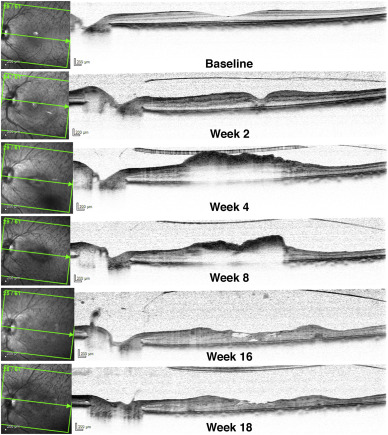

OCT显示与血管渗漏相关的形态学改变。DLAAA处理后第2周可见凹下结构紊乱和高反射。观察到广泛的神经纤维层和视网膜内水肿,第4周开始明显,持续到第10周;这些早期病理改变在16周和18周时发展为退行性囊性改变和视网膜内萎缩。从第2周到第8周,黄斑区视网膜明显增厚,而黄斑周围区域则出现视网膜变薄。此外,视网膜的层状结构杂乱无章。

图3、OCT显示DLAAA视网膜的形态学改变。OCT检查显示血管渗漏相关的形态学改变。第2周可见凹下结构紊乱和高反射率。广泛的视网膜水肿从第4周开始一直持续到第10周。在第4周和第8周还观察到了高反射性并伴有阴影和反射不足,在第16周和第18周观察到退行性囊性变和视网膜内萎缩。结果,从第4-8周开始,黄斑区视网膜增厚明显,而黄斑周围区域的视网膜变薄。